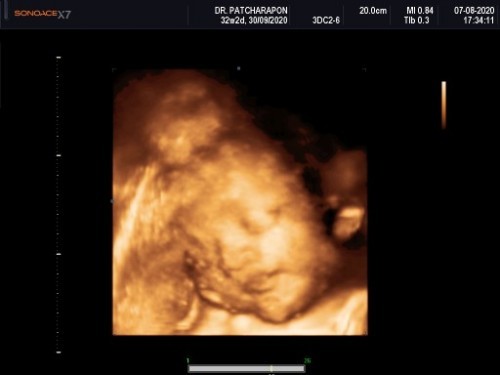

มีใครเคยไปซาว แล้วน้ำหนักน้องเกินเกณ์ กำหนดคลอดเลย เลื่อนขึ้นมาเรวกว่าเดิมบ้างค่ะเราต้องยึดวันคลอดวันไหนค่ะ 32 week 2วัน กำหนด 30กันยา พอซาวรอบนี้น้ำหนัก 2โล3 กำหนดคลอด 16กัยา ค่ั😀😀